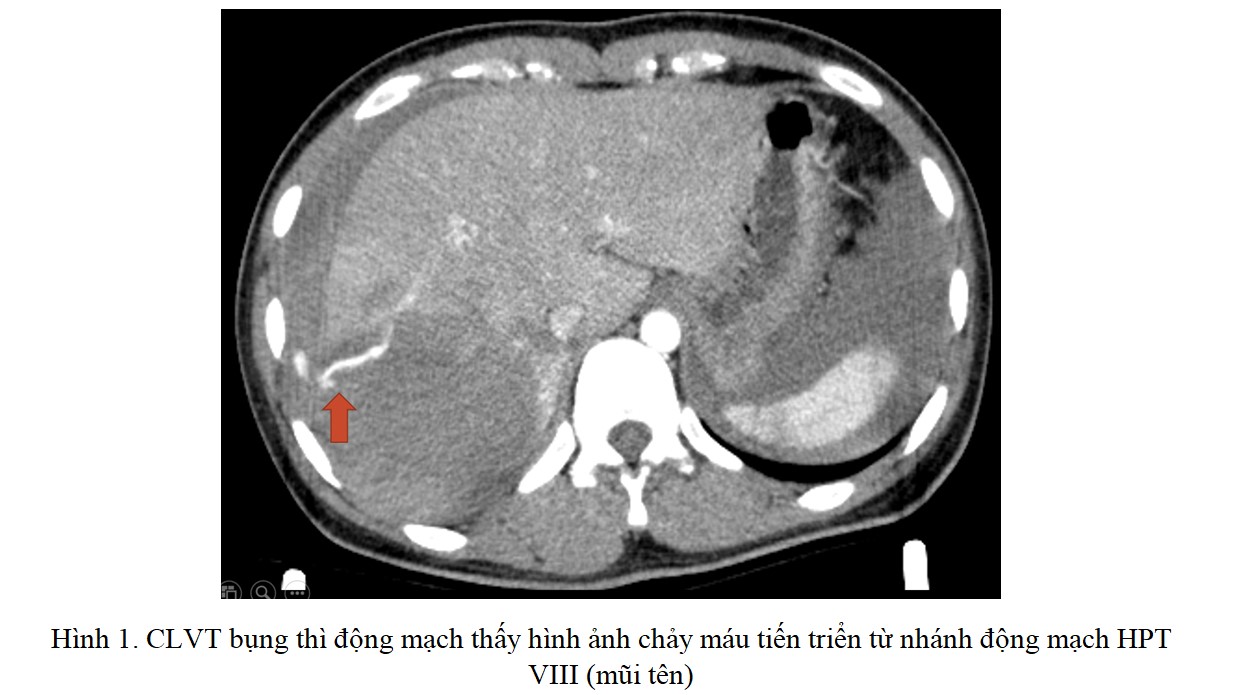

Bí tiểu cấp do chèn ép chùm đuôi ngựa trên bệnh nhân thoát vị đĩa đệm cấp: Báo cáo 2 trường hợp lâm sàng

ThS. Đinh Thị Phương Hoài, ThS. BSCKII. Nguyễn Thanh Minh, ThS. Nguyễn Vĩnh Lạc, BSNT. Trần Thị Mai Diệu, PGS.TS. Nguyễn Khoa Hùng.